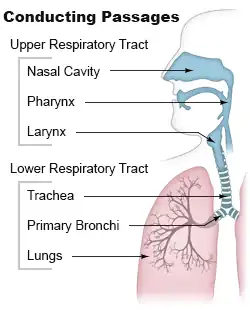

| Diagram of the upper respiratory tract. | |

Pulmonary aspiration is the entry of solid or liquid material such as pharyngeal secretions, food, drink, or stomach contents from the oropharynx or gastrointestinal tract, into the trachea and lungs.[1] When pulmonary aspiration occurs during eating and drinking, the aspirated material is often colloquially referred to as "going down the wrong pipe".